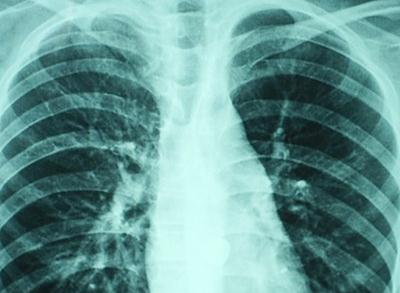

5.X線胸片:大片狀陰影,多見(jiàn)肺底和中部,個(gè)別為粟粒狀陰影,但在短期內(nèi)可有變化。

8.臨床癥狀輕而肺部X線征象嚴(yán)重;使用抗生素,病勢(shì)惡化;用抗真菌藥物治療顯效。